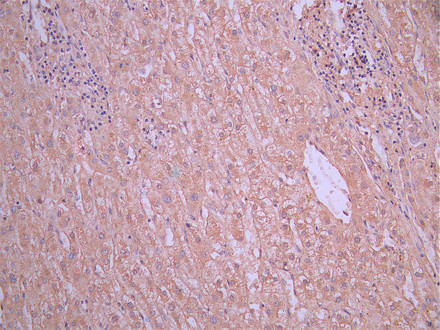

IHC image of CSB-RA001939MA1HU diluted at 1:50 and staining in paraffin-embedded human liver cancer performed on a Leica BondTM system. After dewaxing and hydration, antigen retrieval was mediated by high pressure in a citrate buffer (pH 6.0). Section was blocked with 10% normal goat serum 30min at RT. Then primary antibody (1% BSA) was incubated at 4°C overnight. The primary is detected by a Anti-Human lgG, Fcy Fragment Specific labeled by HRP and visualized using 0.05% DAB.